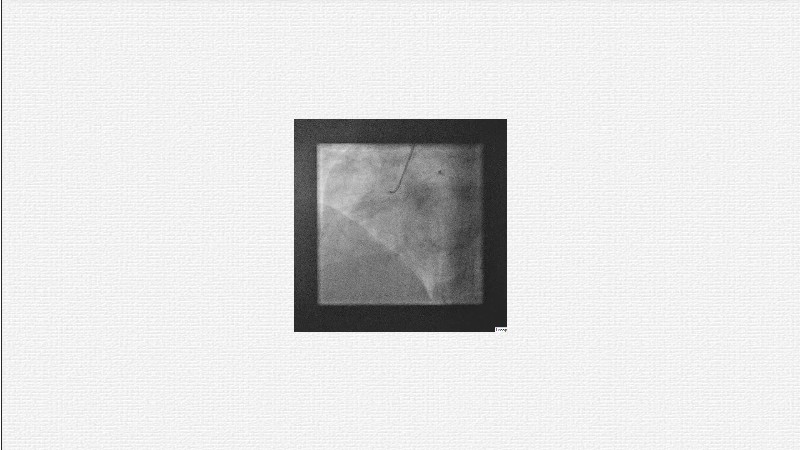

This EuroPCR 2025 session challenges the conventional approach to bifurcation PCI and dissection management. Learn why drug-coated balloons (DCB) may offer better long-term outcomes in cases where stents fall short, how DCBs can simplify bifurcation strategies, and why it’s time to rethink which dissections really need stenting. Through data, case examples, and clear decision-making insights, you'll gain the confidence to broaden your DCB practice where it truly matters.

- To reflect on when to use drug-coated balloons and stents